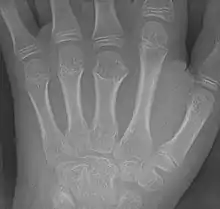

Brachymetacarpia or brachymetacarpalia is a medical condition in which the metacarpal bones of the hands are shortened.[1] The equivalent condition in the foot is brachymetatarsia, in which the metatarsal bones are shortened. Brachymetacarpia is typically congenital and presents in childhood or early adolescence, but it can also be associated with other acquired syndromes or endocrinological conditions. While cosmetic appearance is the most common concern of affected individuals, brachymetacarpia may also affect hand function due to alterations in muscle and tendon length. Treatment usually involves lengthening of the affected bone(s), either acutely with a bone graft or gradually with an external fixator.[2]

This condition is one of the causes of brachydactyly.

Prevalence of brachymetacarpia is unknown. The third, fourth, and fifth metacarpals are most commonly affected.[2]